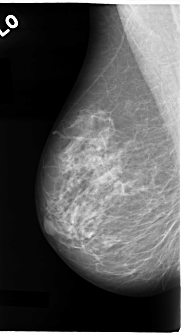

C_0087_1.RIGHT_MLO

DATE_OF_STUDY 11 5 1994

PATIENT_AGE 58

FILM_TYPE REGULAR

DENSITY 2

RIGHT_CC LINES 4656 PIXELS_PER_LINE 2800 BITS_PER_PIXEL 12 RESOLUTION 50 NON_OVERLAY

RIGHT_MLO LINES 4688 PIXELS_PER_LINE 2528 BITS_PER_PIXEL 12 RESOLUTION 50 NON_OVERLAY